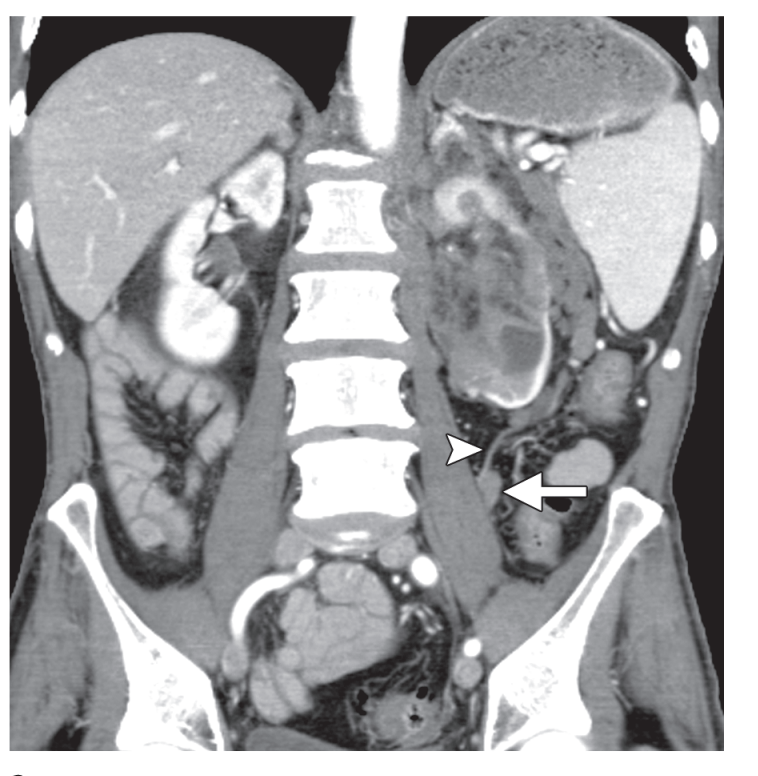

Figure 13. Interfascial spread. (a) Diagram drawn in the sagittal plane shows the inferior fusion of the Gerota (GF) and Zuckerkandl (ZF) fascias, which form the combined interfascial plane (CIP). Although the perirenal space is cut off by the fusion of Gerota and Zuckerkandl fascias inferiorly, it is possible for disease to extend along the combined interfascial plane. (b) Coronal reformatted CT image obtained in a 75-year-old man with nonHodgkin lymphoma shows involvement of the left kidney (*) and perinephric space (black arrow) by tumor and thickening of Gerota fascia (white arrows). (c) Coronal CT image, obtained in the same patient, shows a nodule (arrow) in the combined interfascial plane (arrowhead), a finding indicative of interfascial spread of lymphoma.